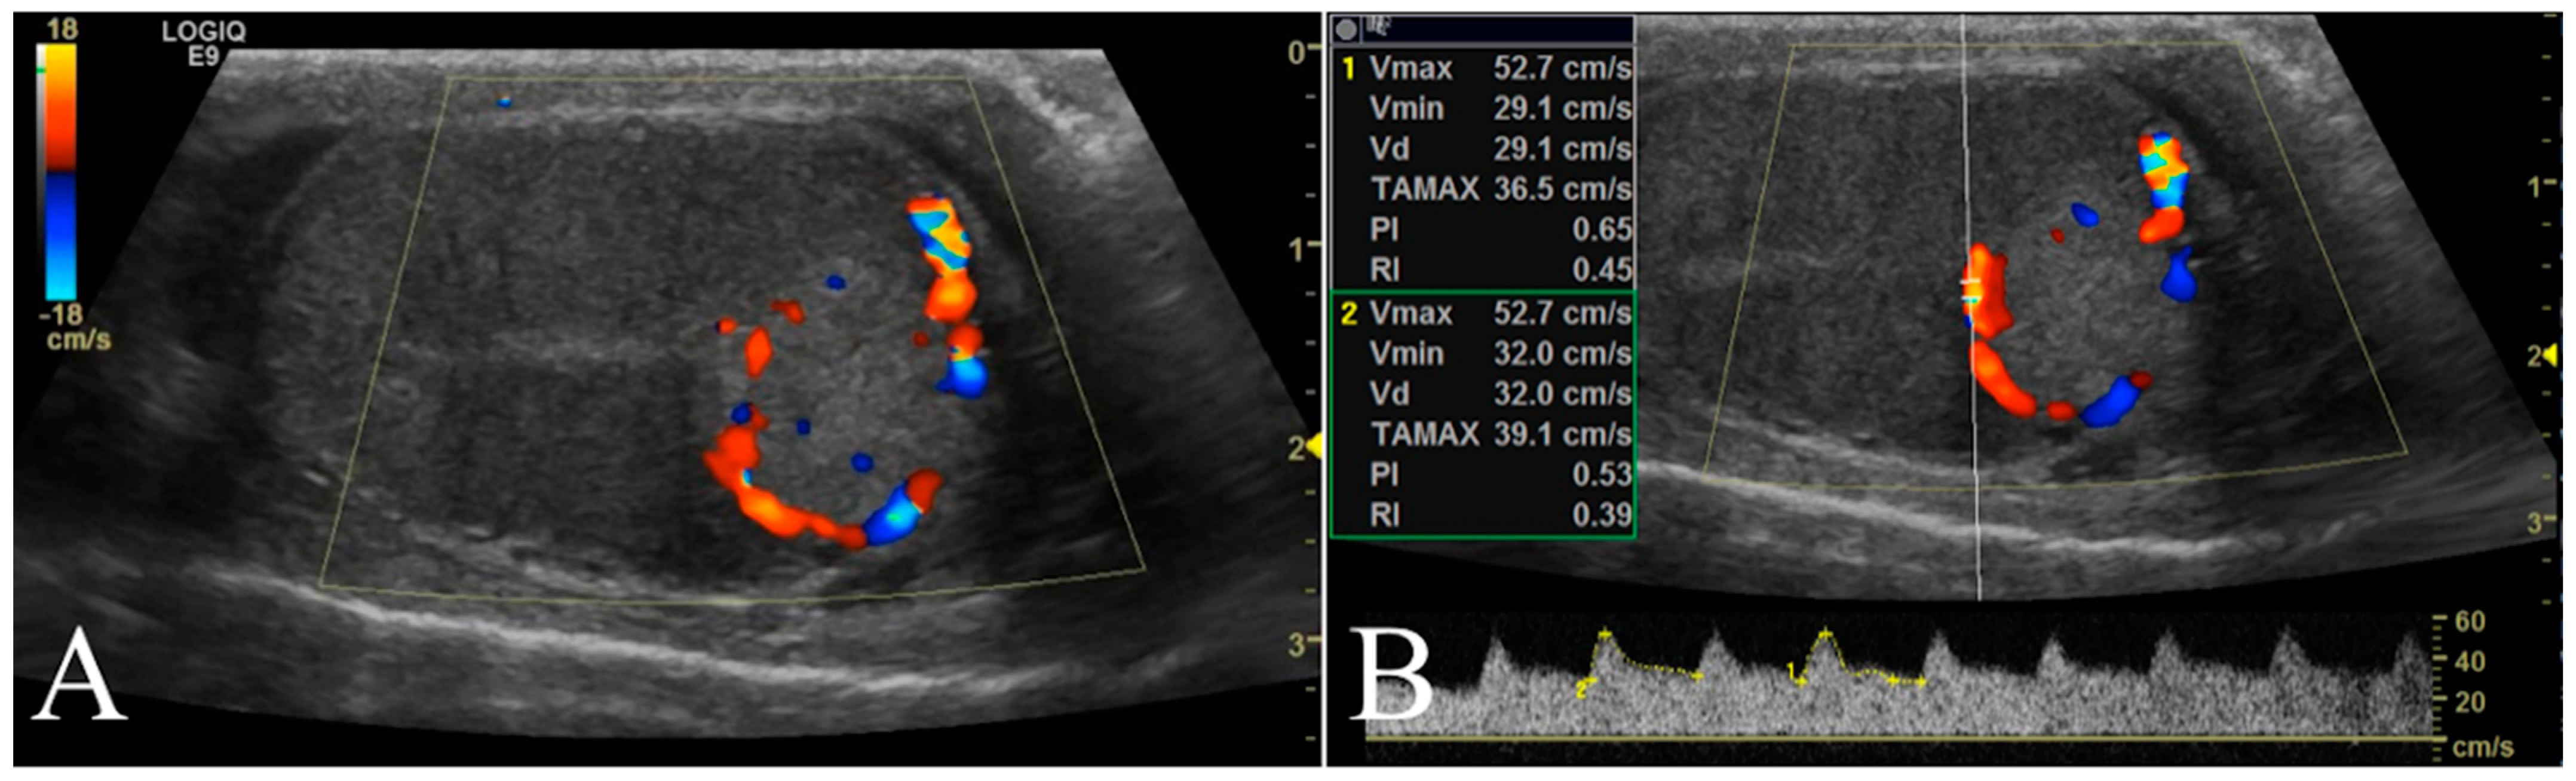

The testicular artery was first detected in the pampiniform plexus by scanning the cranial pole of the testis. Then, the linear probe was moved towards the ventral region of testis to locate the marginal artery. Finally, the ultrasound beam was oriented to optimize the visualization of any lesions present and characterize their blood flow. Based on color Doppler imaging, the blood flow of the lesion was classified as either absent or present and, in such a case, as peripheral or intralesional (Figure 2A). Using pulsed wave mode, a sample volume was successively placed on the pampiniform plexus as well as marginal and lesion arteries (if present) to record the waveforms of at least three consecutive cardiac cycles. The PW was set as follows: frequency 3.1 MHz, pulse repetition frequency 3.3 kHz, and Gain 41 dB. The sample volume, the region where the vessel was studied, was positioned in the artery that allowed the best insonation angle when both peri and intralesional vessels were detected simultaneously in the same lesion. The insonation angle between the Doppler stream and the course of the vascular segment was manually aligned and the measured blood flow velocity was automatically corrected. The measurements with an angle >20° were disregarded. However, the measurements of three different waveforms in each vessel were taken and we made an average to reduce any errors. For each testicular artery, quantitative blood flow analysis included the evaluation of peak systolic velocity (PSV), end diastolic velocity (EDV), resistance index (RI), and pulsatility index (PI) (Figure 2B).

Figure 2. Representative Doppler characterization of a nodular lesion (leydigoma) found in the left testicle of a 11 year old Italian Mastiff. In particular, picture 2 (A), recorded by color Doppler, allowed the visualization of blood flow distributed peripherally to the lesion, while picture 2 (B) showed the same blood flow sampled by pulsed wave mode for quantitative analysis.